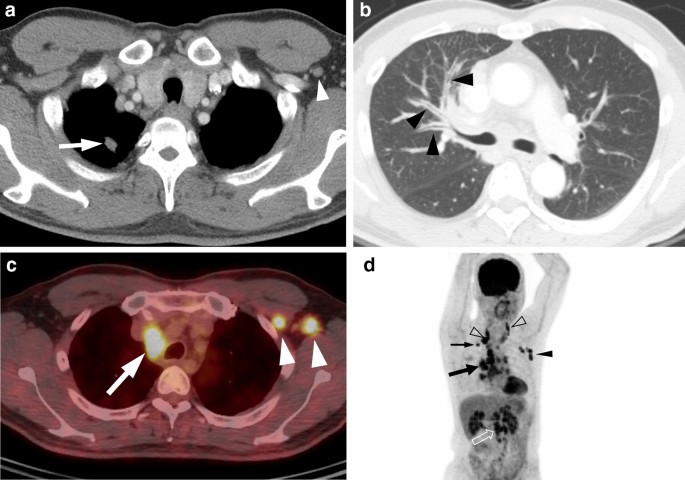

A 44-year-old man with ROS1-rearranged lung adenocarcinoma with extensive lymph node metastases. (a) Transverse mediastinal CT image demonstrates a small solid nodule (arrow) in the right upper lobe, which is presumed to be a primary tumor. Left axillary lymph node enlargement (arrowhead) is also noted. (b) Transverse lung window CT image shows diffuse bronchial wall thickening (arrowheads), which represents lymphangitic carcinomatosis. (c) Fused PET/CT image demonstrates fluorodeoxyglucose (FDG)-avid right paratracheal (arrow) and left axillary (arrowheads) lymph nodes. (d) Maximum intensity projection image of PET shows intense FDG uptake in the primary tumor (thin arrow), cervical (open arrowheads), mediastinal (thick arrow), left axillary (arrowhead), and intraabdominal (open arrow) lymph node metastases.

CT features of the primary tumor and disease spread patterns according to the three genotypes are summarized in Table 2. Lung adenocarcinomas with ROS1 rearrangement were mainly solid in density (19 of 23, 83%) (Figs. 1, 2 and 3), similar to EGFR-mutant (73%) or ALK-rearranged (88%) tumors, and tended to have a lobulated border (15 of 23, 65%). Compared with EGFR-mutant tumors, ROS1-rearranged tumors were less likely to have air-bronchogram (p = 0.011) and pleural retraction (p = 0.048) but more likely to have pleural effusion (p = 0.025), pericardial metastases (p < 0.001) (Fig. 3B), intrathoracic and extrathoracic lymph node metastases (p = 0.047 and 0.023, respectively) (Figs. 1, 2, 3), and brain metastases (p = 0.017). ROS1- and ALK-rearranged tumors showed similar CT features and no significant differences except for pericardial metastasis, which was more frequent in ROS1-rearranged tumors but statistically insignificant (p = 0.060).